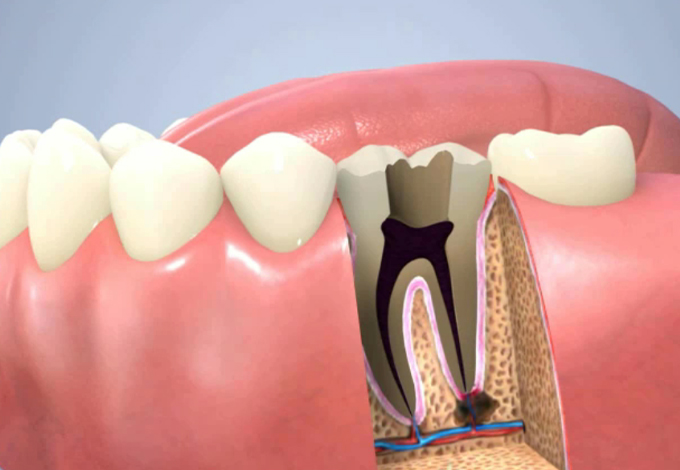

虫歯が歯髄まで達し根尖の先に膿がたまっています

ファイルと呼ばれる器具で壊死した歯髄を取ります。

ファイルが根に到達した時痛みが伴います。